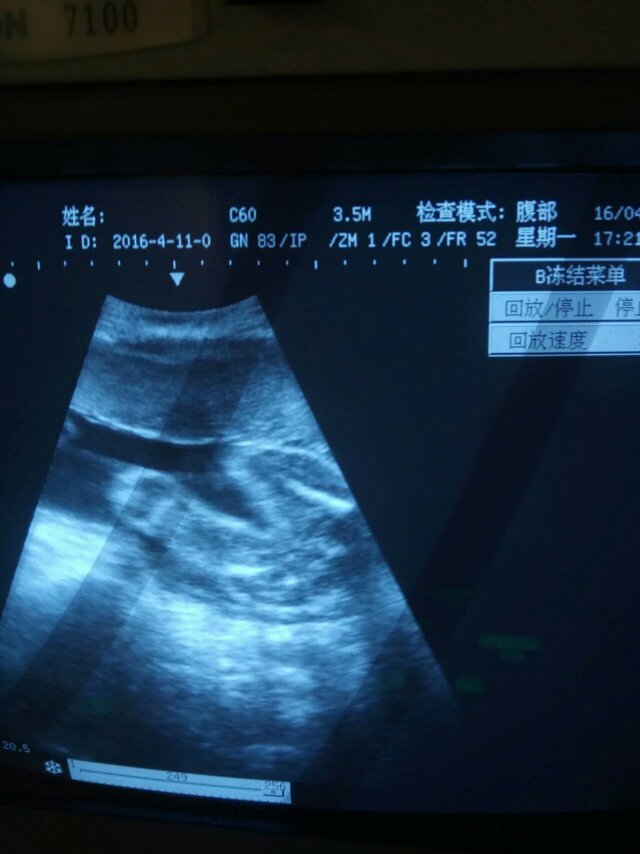

孕六个月黑白b超两次,她说十分清楚,就是女孩,有图,有懂得帮我看看,真的是女孩吗? 点击展开 匿名用户 2016-04-16 21:15 满意回答 亲相信科学吧,是男孩的话不到三个月就可以看出来 131*****262_t2Ki 2016-04-16 21:17 宝宝知道提示您:回答为网友贡献,仅供参考。 为您推荐: 其他回答 不懂,女孩子挺好的,现在女孩最吃香 称慧心_Y1Oo 2016-04-16 21:16 健康就好 匿名用户 2016-04-16 21:15 是女孩 匿名用户 2016-04-16 21:15 男女都一样 匿名用户 2016-04-16 21:15 相关问题 请问我怀孕六个月时去照黑白B超,医生说是女孩,但我的肚子很小又尖,朋友见到都说是男孩,究竟B超准不准 怀孕到现在长了16斤,孕30+3天,16周B超是女孩,自己希望是个男孩,保佑我生个男孩! 怀孕40天,B超孕囊大小1 2*0 7*1 0cm,是不是小了?能看出来是男孩还是女孩吗?